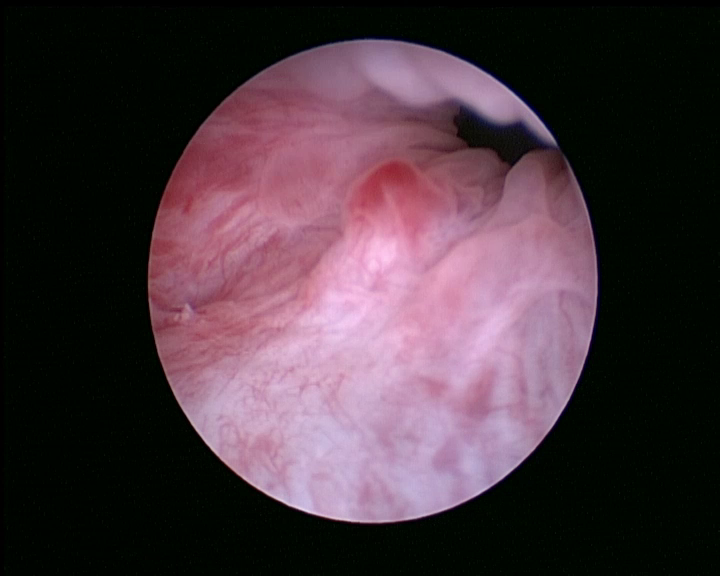

Pour prévenir cette maladie, seule la consommation de foin (foin de Crau ou de phléoles) ou d'herbe fraîche permet l'usure efficace des molaires. Les signes de malocclusion sont des signes de salivation, de refus de s'alimenter, de l'amaigrissement et l'apparition de sécrétions oculaires. En cas d'infection, on observera l'apparition d'abcès dentaires. Le traitement fait appel à la taille des dents sous anesthésie (appelée parage dentaire) par un vétérinaire spécialisé. Cette taille de dent est, si possible, réalisée à l'aide d'une caméra endoscopique pour examiner les dents localisées dans le fond de la cavité buccale et évaluer des lésions plus discrètes.